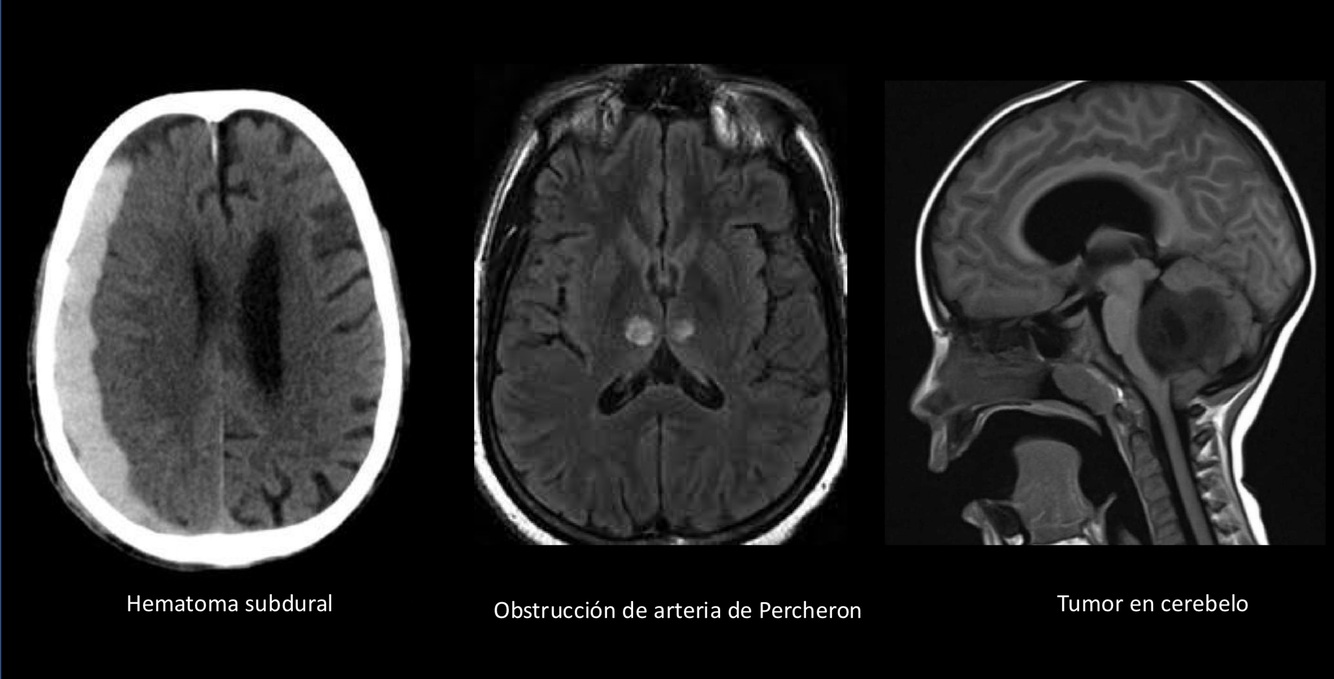

Las dos primeras son supratentoriales y la última infratentorial.

Las obstrucción de la arteria de Percherón ocurre en talamos y causa COMA.